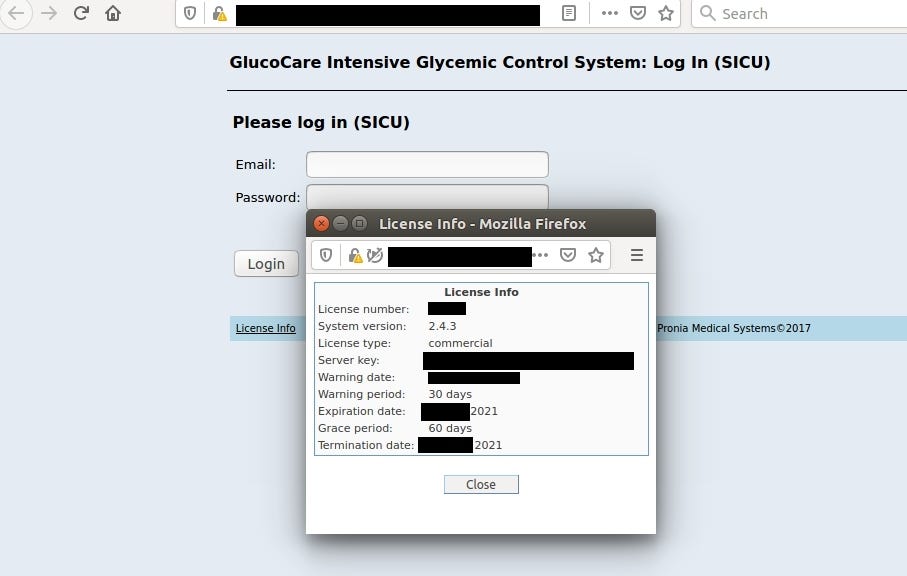

GlucoCare Glycemic Control System

Insulin dose calculation software developed and marketed by Pronia Medical Systems https://proniamed.com

It reveals server key and license info in login panel